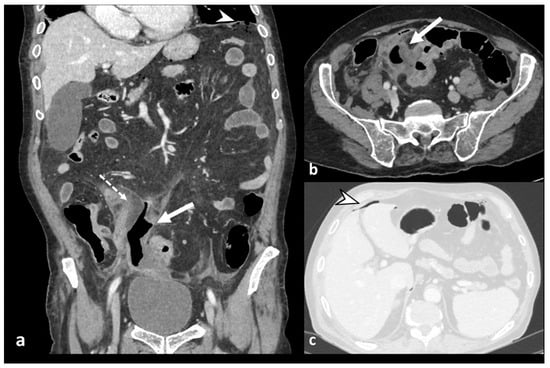

Figure 6. Axial and coronal contrast-enhanced CT images (a,b) show an abscess, a fluid-containing mass with air and an enhancing wall (white arrow), near the inflamed colonic tract (dotted arrow) and signs of perforation, with distant air bubbles below the left hemidiaphragm (arrowhead in (a)); lung window axial CT image (c) shows distant free air anteriorly to the liver (arrowhead).

The severe inflammatory state of the colonic wall could lead to mural necrosis and perforation of the bowel [25]. Free air can be well-contained and self-limiting, consisting of localized gas adjacent to the inflamed colon (air bubbles or pockets), or it can spread into the intraperitoneal or retroperitoneal cavity [5,8]. Pericolic free air is defined as the presence of air bubbles or air collection within 5 cm of the inflamed bowel segment without distant air (Figure 5), or distant free air collections in the abdominal or retroperitoneal cavity with a distance >5 cm from the inflamed bowel segment (Figure 6) [11]. CT can detect signs of perforation, including bowel wall discontinuity and extraluminal air, especially using lung window settings (Figure 6) [26].

Diverticulitis can cause abscess formation. An abscess is defined as a fluid-containing mass with or without air and an avidly enhancing wall that can be intramural, pericolic, or distant from the inflamed colon (Figure 6 and Figure 7). It is necessary to report the inflamed colonic tract’s localization, the abscess’s maximum diameter (<4 cm or ≥4 cm), and the anatomical relationships with the surrounding structures, especially intestinal loops or organs, with which fistulas can develop. Regarding the dimensions, a diameter greater than or equal to 4 cm indicates percutaneous drainage (Figure 7) [8,10].